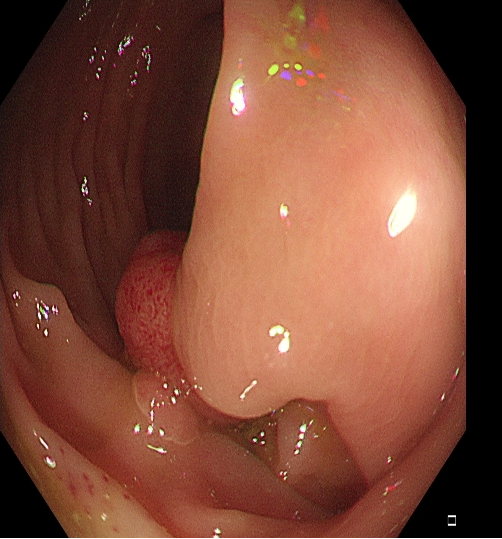

适用于不同大小隆起型病变Ⅰp型、Ⅰsp 型以及小型(<2 cm)Ⅰs型(具体分型标准可参照内镜发现消化道早癌,分型太多不知道怎么判断?这篇文章讲清楚了)病变的切除。小型Ⅰp型病变,圈套切除相对简单,可采用冷或热圈套切除,切除时应在保证完整切除病变同时,保留一定长度的蒂部或与肠壁保持一定距离,收紧圈套后,应抖动圈套器,观察有无周围正常肠黏膜一并套入,防止损伤肠壁。

图2 小型Ⅰsp 型病变热圈套切除示意图